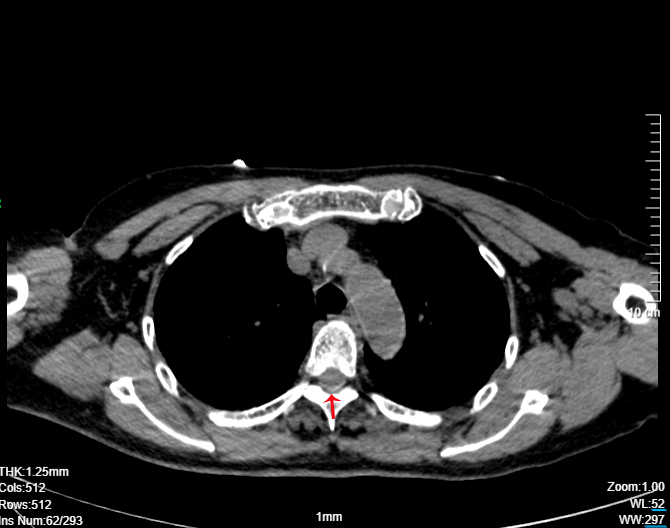

谢方民联合麻醉科主任医师张文生、副主任医师李波和影像科主任医师秦健、闫呈新、王峰进行多学科讨论后,为丁阿姨制定了治疗方案——患者被诊断为自发性脑脊液漏,低颅压成立,决定给予硬膜外血贴疗法。经过充分术前准备,治疗团队根据脑脊液漏点进行术中彩超和C—型臂联合精准定位后,抽取患者自体静脉血15ml,缓慢注入胸椎脑脊液漏点附近,术中给患者打了一个安全贴心的“血补丁”。目前患者经过两周卧床休养,已经开始下地行走,症状明显好转,在进一步的康复中。

术后复查:血贴的位置(红剑头),血贴覆盖4个椎体(T3-6)